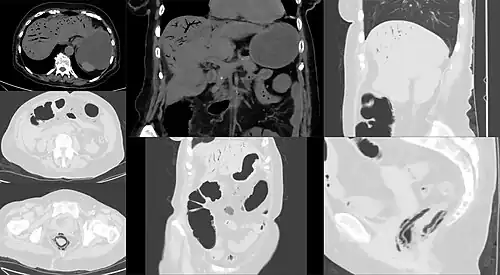

| Computed tomography (CT) showing dilated loops of small bowel with thickened walls (black arrow), findings characteristic of ischemic bowel due to thrombosis of the superior mesenteric vein. | |